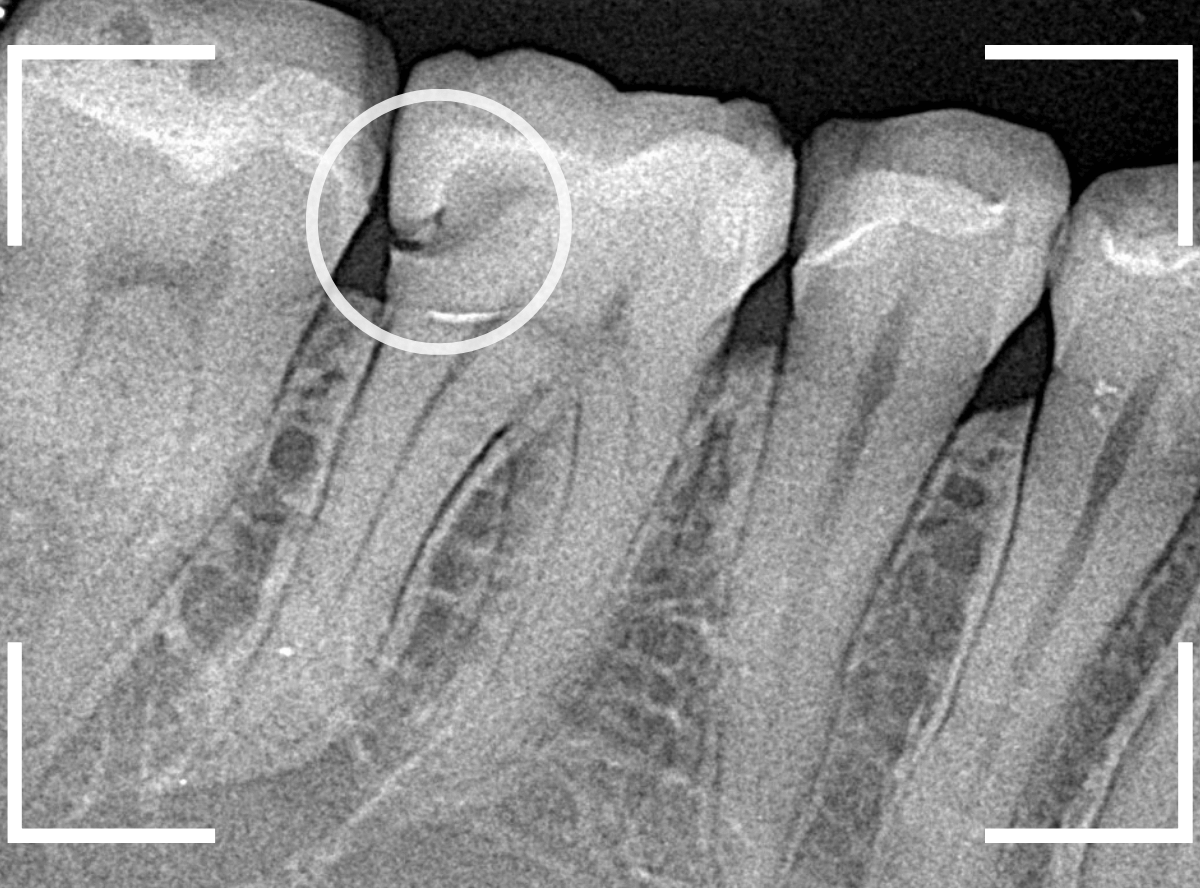

まずは、レントゲン写真で歯の内部を確認します。

幸い歯が欠けたのは表面のみで済んでいましたが、矢印の歯の土台(コア)からしっかり作り直したいのですが、細い歯に金属ピンの部分が歯の根までしっかり入っているので、これを外すのはかなり大変そうです(><)

過去に治療したセラミック・インレーが不適合になっているのが、レントゲン写真で見つかりました。

後ろの歯とのすき間の部分が欠けてしまったのか、不適合になり、中で虫歯が進行しているように見えます。